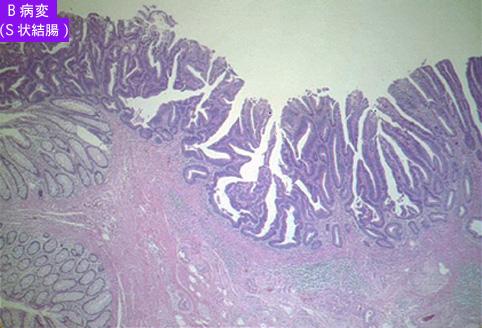

疾病(病理主体)的分类恶性上皮性肿瘤/腺癌

部位(按器官分)大肠/乙状结肠

检查方法病理切片(微观)

肿瘤的肉眼分类0型(表在型)/IIa型(IIa+IIc)

肿瘤最大直径15~19

肿瘤的深度sm